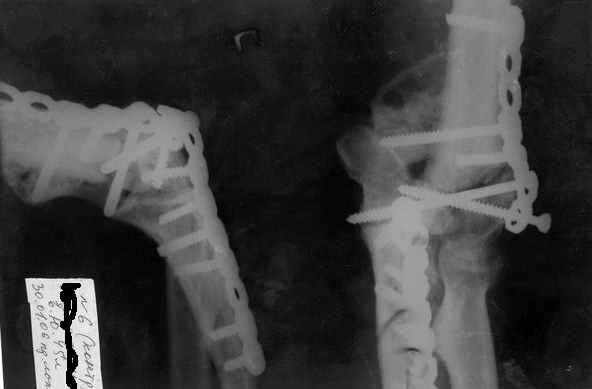

100%-эндопротезирование полужестким имплантатом типа Coonrad-Morrey(Zimmer),GSBIII (Sulzer) или АРЕТЕ(питерская фирма).

В РНИИТО им.Вредена опыт около 55 операций, в том числе после травм. Результаты в целом хорошие.

Э\п-е даёт стабильный сустав, без боли, хорошую функцию. по всем шкалам отлич. результат,если объём движений в локтевом суставе 90град.

Для данного пациента может потребоваться изготовление индивидуального протеза с длинной ножкой.